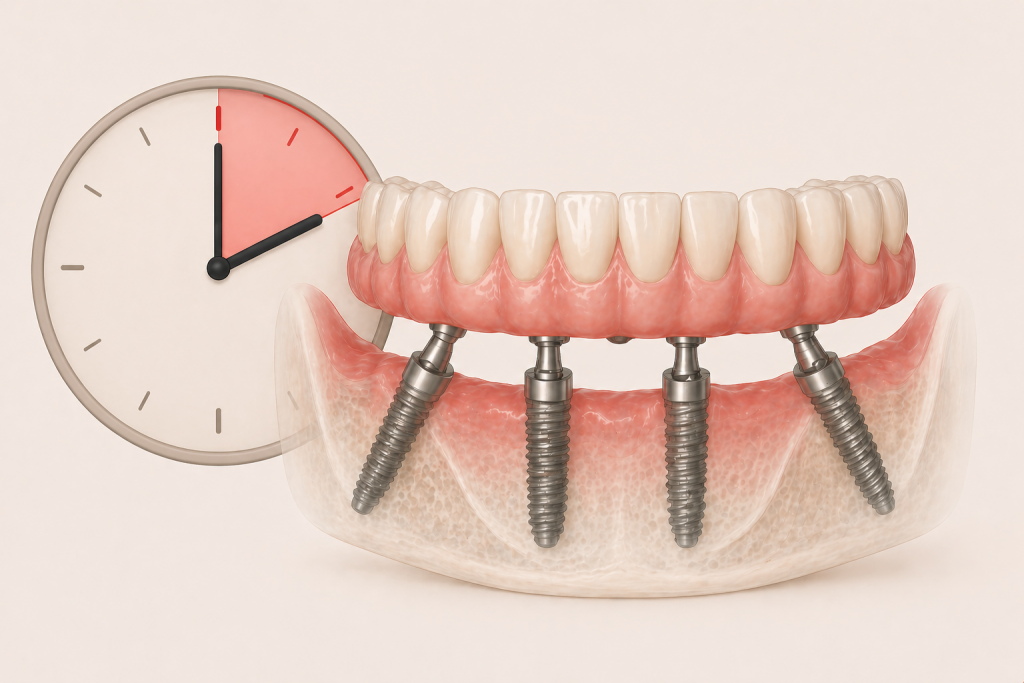

Il carico immediato: quando si può fare davvero

Spesso si parla di denti fissi “in un giorno”.

Nella pratica clinica, il carico immediato significa questo: gli impianti vengono inseriti e, entro poche ore o entro 24 ore, viene applicata una protesi provvisoria.

Nel nostro approccio, questa protesi è stabilizzata su una struttura in titanio.

Generalmente preferiamo il carico immediato nelle nostre riabilitazioni implantari, tuttavia non è una scelta automatica.

Il carico immediato è possibile solo quando:

- gli impianti hanno una stabilità adeguata

- l’osso lo consente

- le condizioni generali sono favorevoli

Quando queste condizioni non sono presenti,

è più corretto attendere. Forzare i tempi non migliora il risultato.